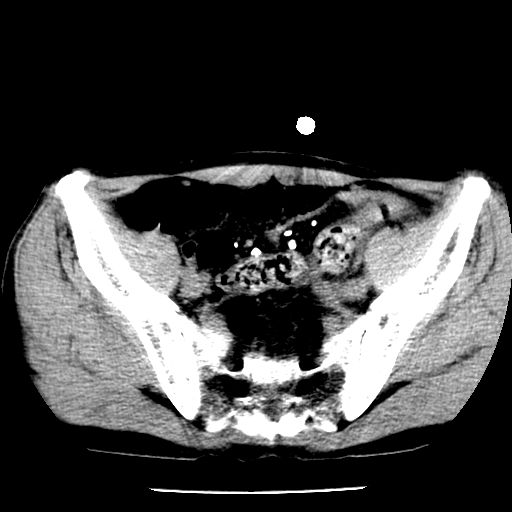

男,59岁,“结核性胸膜炎”30余年,胸部经常疼痛,多次x检查提示“肺部”炎症。腹部疼痛5日,b超提示:“肝内短管结石,余显示不清,建议进一步检查。”

两肺结核并右侧胸腔积液;脾脏、腹腔及腹膜后淋巴结结核[陈旧性];肝内胆管结石

胸部腹部都是结核(双肺。纵隔淋巴结,肝脏,脾脏,肠系膜)

两肺结核并右侧胸腔积液;脾脏、腹腔及腹膜后淋巴结结核[陈旧性];肝内胆管结石。直肠息肉?